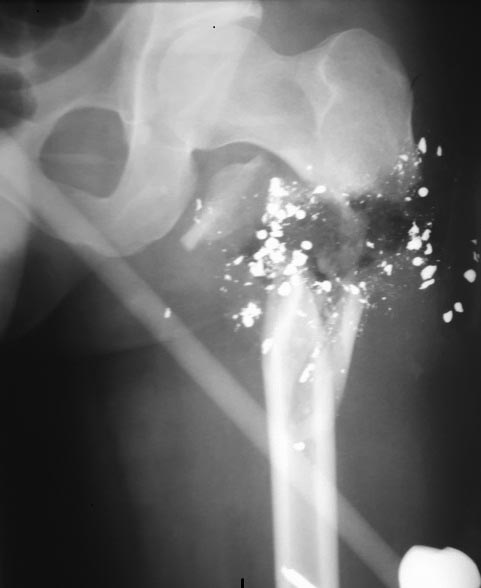

Re: Огнестрел. Перелом бедра с дефектом кости

Мягкие ткани - воспаления нет, рана в вертельной области после ПХО под VAC терапией. По поводу проксимального гвоздя - проксимальный отломок очень короткий, думаю от варуса уйти будет проблематично. И шеечный винт(ы), клинок будет проходить по торцу проксимального отломка, т.е ч\з зону перелома.

Леня, мы сейчас межвертельные остеотомии гвоздями фиксируем, а тут вообще не видно проблем с вальгизацией центрального отломка. А винты главное чтобы в головке и шейке правильно располагались, а в дефекте пусть цементное покрытие будет. Поэтому лучше взять рекон., чтобы и с цементом диаметр был не больше, чем у PFN без цемента.

Леонид, думаю, острое укорочение, сращение, а потом уже думать об удлинении. Так более безопасно

Согласен с выбором в пользу аппарата, вероятность нагноения погружных

конструкций велика

Мне представляется, что надо сделать закрытый интрамедуллярный остеосинтез реконструкционным гвоздиком, покрытым цементом с антибиотиком. Без укорочения. То есть восстановить длину бедра как есть. Это типа того же аппарата, что и сейчас, но внутри. И с рассверливанием, чтобы в дефект попал reaming debris.

А дальше - есть и шанс, что какая-то спаечка образуется и так, с гвоздем внутри самой маленькой "скобочки" достаточно. Или Masquelet, или остеотомировать диафиз (со стержнем внутри это получается) и сделать транспорт, отталкиваясь от дистального отдела бедра.

Мы бы наверно выполнили бы БИОС с АБ, так же как советует Александр Николаевич.

Есть несколько больных после огнестрельных переломов на разных уровнях - всех лечили стержнями с АБ покрытием. Ближайший результат не плохой, отдаленных пока нет.

Леня, самую тонкую длинную Гамму

с ШДУ углом 120 гр.

1 этап стабилизация.

2 этап дистракция на стержне

или по Челнокову А.Н., хорошо бы в дефект попала костная стружка,

можно еще добавить PRP

2 этап план В - после сращения перелома - остеотомия и дистракция - возможны варианты, со стержнем, без него с другим стержнем и пр.

Не могу приложить рентгенограммы своего именно такого случая за его неимением, поэтому ограничусь голыми рассуждениями. Хотя, в тоже время, они не совсем голые, так как пациентов с близкими к этой ситуации у нас было не мало.

По моему, надо следовать следующему тезису:

"Не открывать больше зону ранения, как потенциально наиболее опасную в плане нагноения на любом, даже самом отсроченном, этапе; иметь максимальную концентрацию антибиотика вокруг штифта в периоды наибольшего риска воспаления и наименьшей стабильности фиксации".

Я бы сейчас попытался срастить перелом способом, который дает наибольшую вероятность консолидации. Это максимально стабильная фиксация с максимально плотным контактом отломков. Данной задаче более всего соответствует следующее вмешательство (операция №1) - укорочение и синтез штифтом с аб покрытием. После этого - толстый подстопник и как можно больше ходить с максимальной нагрузкой. Здесь еще один вопрос (я пока еще окончательное мнение не сформировал): какой штифт выбрать - цуфаломедуллярный или реконструктивный. Цефаломедуллярный - прочнее фиксации короткого проксимального отломка, но его верхняя часть толще и вынужденно покрытие будет иметь малую толщину слоя и высока вероятность его раскалывания и то, что цемент останется внутри канала при извлечении штифта (это не катастрофа, но не приятно). Реконструктивный - толщину покрытия можно сделать 2-3 мм, оно будет прочнее держаться на штифте, но стабильность фиксации короткого проксимального отломка меньше.

После операции ждем 1,5 - 2 мес. Если воспаления и свищей нет, как только появятся начальные признаки консолидации - (можно надеяться что через 1,5 -2 мес) следующая операция.

Операция №2 - удаляем старый штифт, делаем остеотомию бедренной кости в здоровой зоне (в средней трети), ставим новый штифт со свежим аб покрытием не блокируя дистальные винты, и накладываем спицевой аппарат для дистракции на штифте (провести спицы мимо штифта на бедре труда не составит). После операции начинаем дистракцию до момента полного восстановления длины.

Операция №3 - блокируем дистальные отверстия в штифте и демонтируем аппарат. В послеоперационном периоде опять максимальная осевая нагрузка и ЛФК.

Травматологи отлично справились с очень сложной ситуацией. На фоне кровопотери, размозжения тканей, множества инородных тел – остеомиелита нет. С учетом возраста, требований пациента к качеству жизни, состоянию мягкий тканей, устойчивости к антибиотикам (включая наличие или отсутствие дисбактериоза) – планируйте и вариант вмешательства с форс-мажорными обстоятельствами. Предлагаю несколько вариантов лечения аналогичных повреждений.

Рентгенограмма 1:

После ПХО. Наложен спицестержневой аппарат. Вынужденное удаление спицы и стержня. Для предотвращения нестабильности и формирования ложного сустава наложены две стягивающие скобы. После демонтажа аппарата через 2 месяца.

Рентгенограмма 2:

После ПХО. Наложен спице-стержневой аппарат. Дефект закрыть не удалось. В «тихом» периоде выполнена пластика пористым имплантатом. Остеосинтез выполнен пластиной. Фиксация имплантата и пластины выполнена стягивающими скобами.

Рентгенограмма 3:

Рентгенограммы больной У., 52 лет, с околосуставным переломом дистального сегмента бедренной кости (тип А3): а – до операции; б – через 6 месяцев после чрескостного остеосинтеза с использованием аппарата Илизарова; в – после реконструктивной операции замещения костного дефекта пористым имплантатом.

На страницах Форума мы неоднократно разбирали методы лечения ОСП, где общий консенсус на стороне менее агрессивных методов, например, вместо наружных фиксаторов - блокирующий интрамедуллярный гвоздь. О преимуществах интрамедулярного лечения при ОСП написано много, но в странах СНГ до сих пор главным методом является наружный фиксатор (аппарат Илизарова), потому что понятие “не трогать канал” доминирует со времен советского союза!

Все огнестрельные повреждения являются открытыми ранами, и об успешном применении гвоздя было доложено различными авторами еще в середине 80х, где главным применили те же принципы, как при открытых переломах. Принцип работает, и раны 1-2 и 3А степени, и повреждения с низкой энергией после irrigation and debridement можно фиксировать любым из методов: гвозди, пластины или наружный фиксатор.

А при ранениях с высокой энергией, к которым относится дробовые с близкого расстояния, а также ранения из армейского арсенала (Калашников, М-16 и т.д.), которые характеризуются большими повреждениями мягких тканей - требуется этапное лечение. (Ваш случай, сперва на наружном фиксаторе, а потом окончательная фиксация).

С приходом метода вакуумирования ран изменилась этапность лечения. Вакуумирование иногда позволяет обойти первичный этап, т.е сперва добиваемся стабилизации кости, затем занимаемся процедурами по закрытию дефекта мягких тканей. Можно продолжить Irrigation and debridment, а вакуум предупреждает осложнения, создает удобства для обработки раны и экономит время на восстановление.

Наружный фиксатор редко применяется как окончательный для лечения огнестрельных повреждении. Кроме этого, при одном сохранном сосуде после восстановительных операции на сосудах мы рекомендуем только стержневые, а спицевые (аппараты Илизарова) из-за риска сосудистых повреждении не рекомендуется!

В данном случае с первичным этапом справились на хорошо, теперь надо сделать окончательную фиксацию. Дефект кости (укорочение) небольшое и не стоит гоняться до миллиметра восстановить. Не надо укорачивать, и вместо наружного фиксатора фиксировать “как есть” гвоздем!

При рассверливании канала часть стружек попадет в зону дефекта и частично закроет его. Еще в римере остается достаточное количество стружек и при желании через трубку можно их ввести в дефект.

Если рана спереди, тогда топография позволяет безопасно установить гвоздь. Предварительный расчет повзоляет правильно угадать длину и установить шеечно- диафизарный угол! В связи с тем, что все огнестрельные переломы срастаются хорошо, можно не беспокоиться, а при отсутствии сращения через пару-три месяцев можно добавить аутографт.

Для фиксации мы бы выбрали VersaNail Trochanteric Femoral nail, блокировка не параллельные в шейку, а перекрест!

По поводу гвоздя с цементом с антибиотиком, это - идеальный метод для инфицированного канала, или когда лабараторно доказано наличие остеомиелита, но для профилактики свежего перелома мы не имеем данных, что цемент, при отсутствии инфекции окажет благоприятное действие! Так что не объязательно “бить Градом!”.

Полностью соглашаясь с представленной тактикой и отличными результатами лечения огнестрельных переломов мирного времени, вызванных в основном короткоствольным оружием с относительно низкой скоростью и энергией (криминальная травма), хочу отметить принципиально иной подход при лечении высоко-энергетичной боевой травмы (огнестрельные ранения от армейского оружия с высокой скоростью полета пули, минно-взрывная травма, осколочные ранения, РПГ, Град...).

Необходим этапный подход, основанный на принципах damage control, обильное промывание ран и тщательная радикальная первичная хирургическая обработка с открытым ведением послеоперационной раны и последующим вакуумированием, минимально-инвазивная первичная стабилизация переломов наружными фиксаторами (желательно односторонние стержневые аппараты), временная блокировка при внутри- и околосуставных переломах.

В последующем, только после достижения общей и локальной стабилизации пациента, можно перейти к окончательной фиксации переломов (методы внутренней или наружной фиксации), основываясь на состоянии мягких тканей над костными отломками и местом перелома.

Мы успешно используем данную этапную тактику при лечении последствий боевой травмы и лечении жертв террористических атак. В последнее время в плане гуманитарной помощи в нашей больнице прошли лечение более 430 сирийских пациентов - жертв гражданской войны в Сирии. В подавляющем большинстве (более 80 процентов) – сложная ортопедическая травма с обширными повреждениями мягких тканей. Первичная стабилизация аппаратами наружной фиксации у всех пациентов с переломами длинных трубчатых костей (только наружная фиксация!) радикальная ПХО, открытое ведение раны, VAC позволили избежать гнойно- септических осложнений, все пациенты вернулись домой без хронической инфекции и остеомиелита.